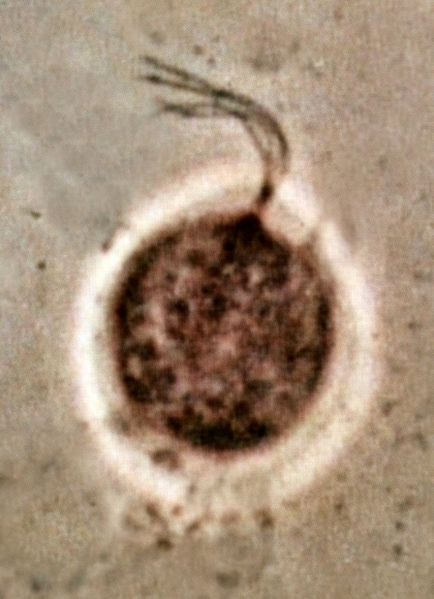

вагинальная трихомонада — возбудитель трихомониаза | дата обновления 15.02.2013Мой мирВконтактеОдноклассники Рубрика: Поделись в соцсетяхВконтактеОдноклассники